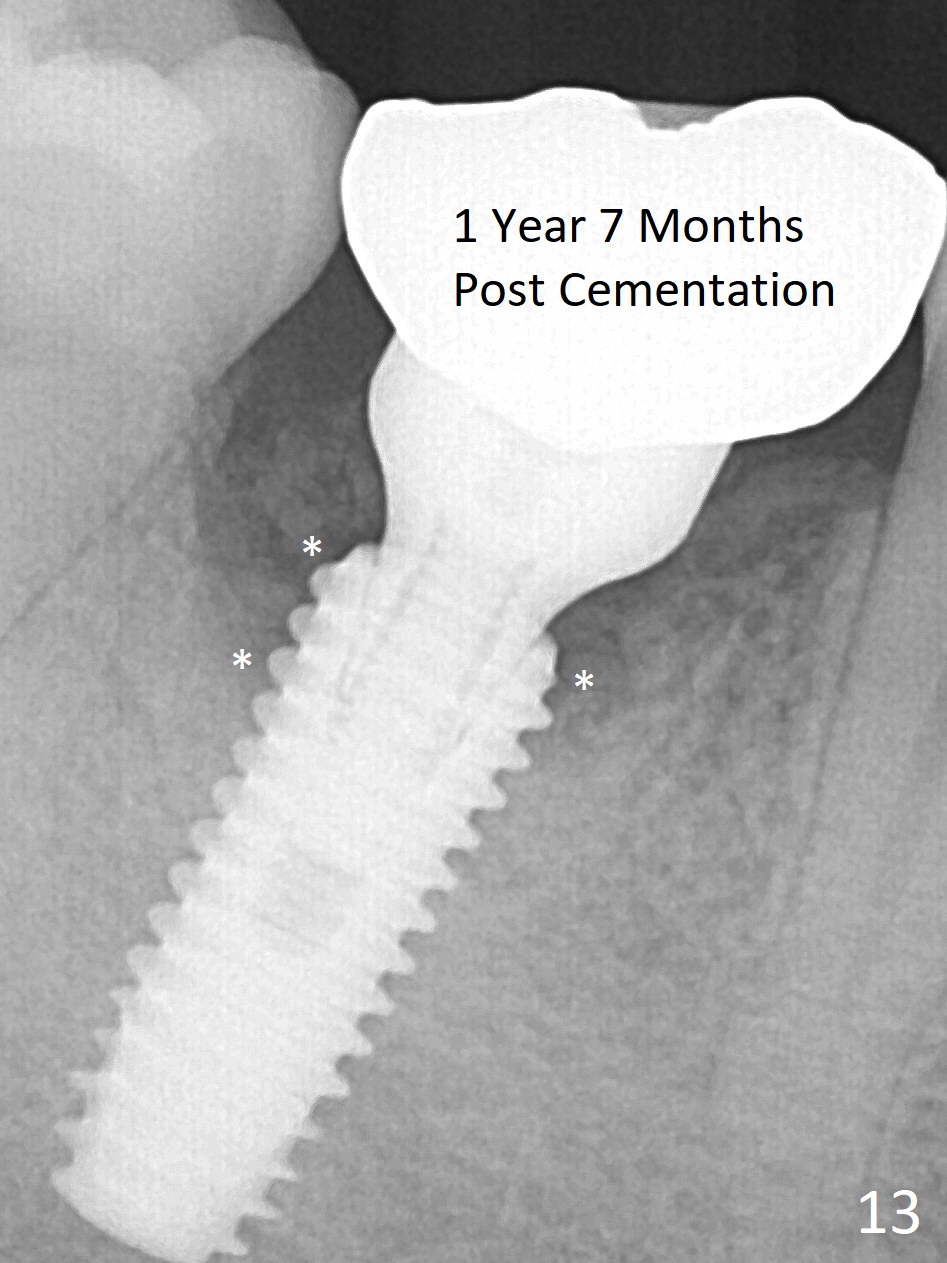

Fortunately no paresthesia is reported postop. Why is the Inferior Alveolar Canal not violated? Fig.7 is a coronal section of CBCT taken for a 40-year-old man at the lower 1st molar (at the septum). At the region, the Canal (brown circle) is close to the lingual plate (L). Because of severe bone loss of the lingual plate of this case (Fig.8 *), osteotomy is intentionally created buccal (green). The deep osteotomy may not contact the Canal, while the hemorrhage may stem from the medullary space (M in Fig.4,7). Bone morphology at the coronal end of the implant apparently changes 4 months postop, suggesting osteointegration (Fig.9). Impression is taken. Bone density around the implant at the crest seems to increase (Fig.10), while there is no soft tissue deficiency 10 months post cementation (Fig.11). The bone appears to regenerate toward the abutment, particularly distally, 14.5 months post cementation (Fig.12). Periimplantitis develops (bleeding on water pik and erythematous and tender buccal gingiva) 1 year 7 months post cementation (Fig.13,14). The 1st three threads are exposed (*). Bone graft with PRF and 6-month membrane or Cytoplast will be needed. Pain disappears 3 days of oral antibiotic. The gingiva looks healthy 1 month later when he returns for bone graft (Fig.15). But the lingual gingival cuff is not so healthy when the crown/abutment is removed (Fig.16 <). Bone graft is not done. For those patients with suboptimal oral hygiene, implants should be placed as low as possible, better with guide for precision.